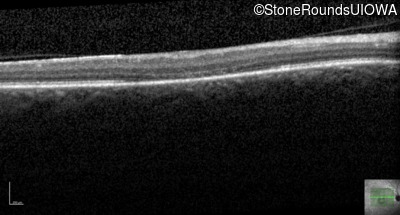

This 44 year old man became photophobic about 6 years ago. He has been taking Imuran since his kidney transplant 23 years ago.

| Senior-Loken Syndrome | NPHP1 | Gly343Arg G(GG)>A(GG) | Deletion of Entire Gene | AR |